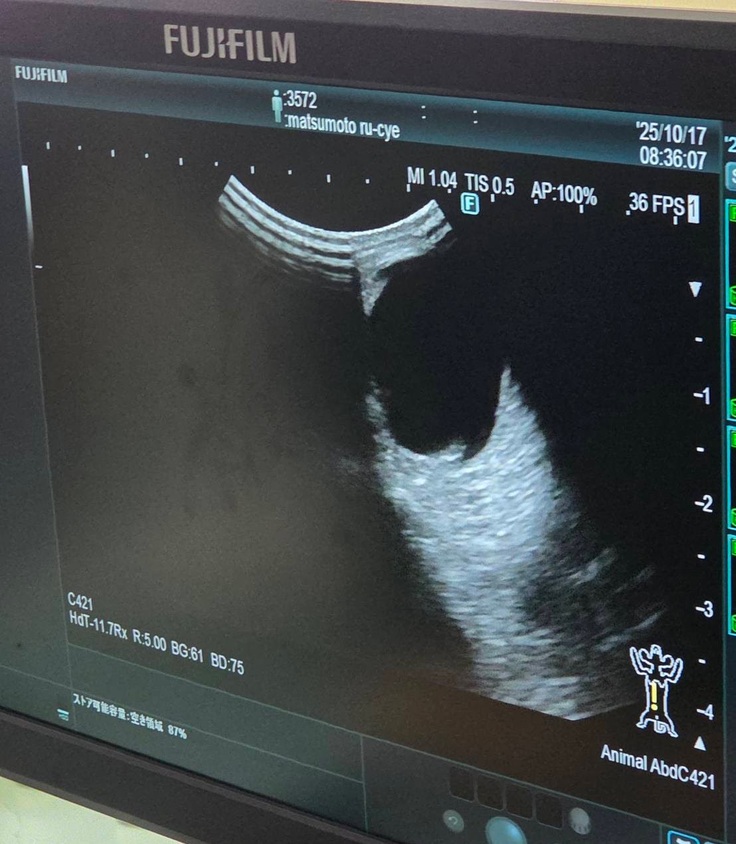

血液検査の写真は撮れなかったのですが、エコー検査では

↓腎臓転移なし

↓肝臓転移なし

↓膀胱転移なし

↓反対側の腎臓も転移なし

※正面から撮りたかったのですが先生がいたので撮れず、見づらくて申し訳ないです。